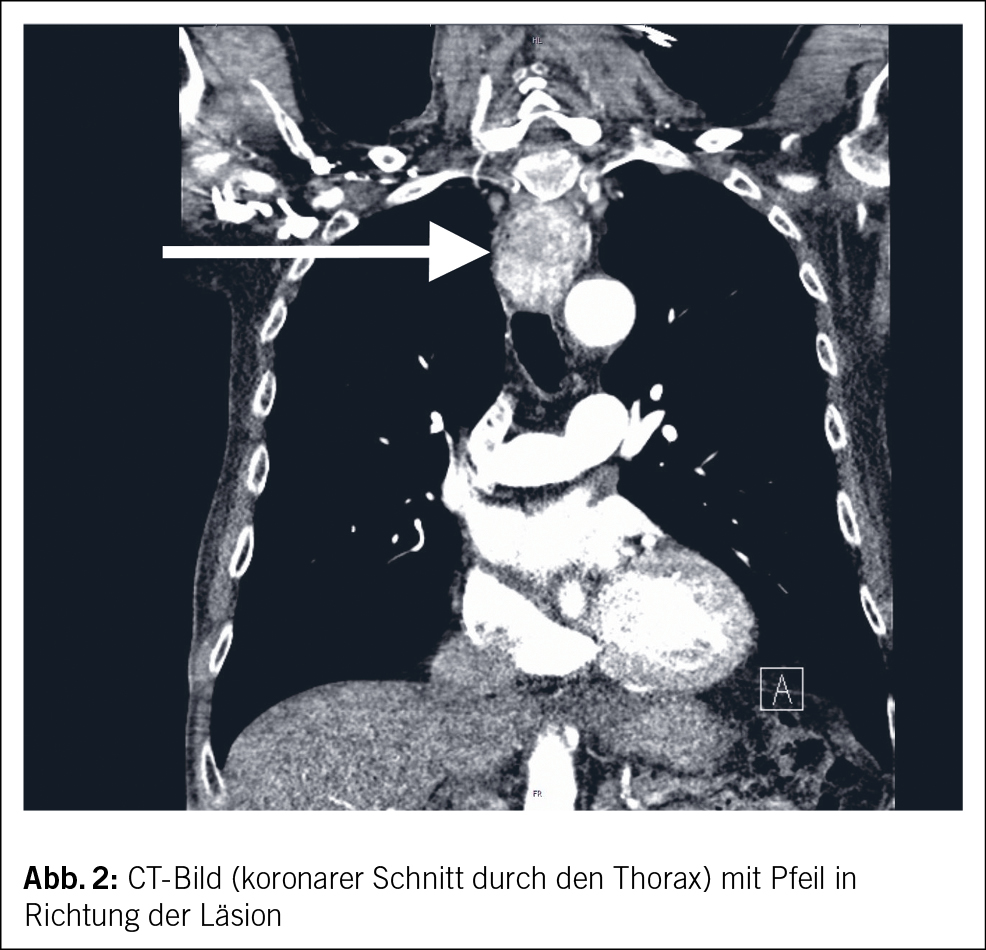

CT-grafisch wurde die Raumforderung dann als ungefähr 3 x 3 x 5 cm grosse Läsion im Bereich des proximalen Ösophagus mit deutlicher Kontrastmittelaufnahme beschrieben (Abb. 2). Die Ätiologie der Raumforderung blieb vorerst aber unklar. Differenzialdiagnostisch wurde von den Kollegen der Radiologie ein neuroendokriner Tumor, ein gastrointestinaler Stromatumor, ein Leiomyom oder ein ektopes, hyperproliferiertes Schilddrüsengewebe postuliert. Der Patient wurde auf der Station weiter klinisch überwacht, mittels hochdosierter Protonenpumpeninhibitoren (PPI) behandelt, und das Hämoglobin wurde engmaschig kontrolliert und eine erneute endoskopische Abklärung in Endosonografie-Bereitschaft geplant. In der erneuten gastroskopischen Untersuchung konnte der Befund nochmalig dargestellt werden, und es gelang die Entnahme einiger Proben zur histologischen Untersuchung. Auf eine obere Endosonografie wurde bei deutlicher Lumeneinengung durch den Befund vorerst verzichtet.